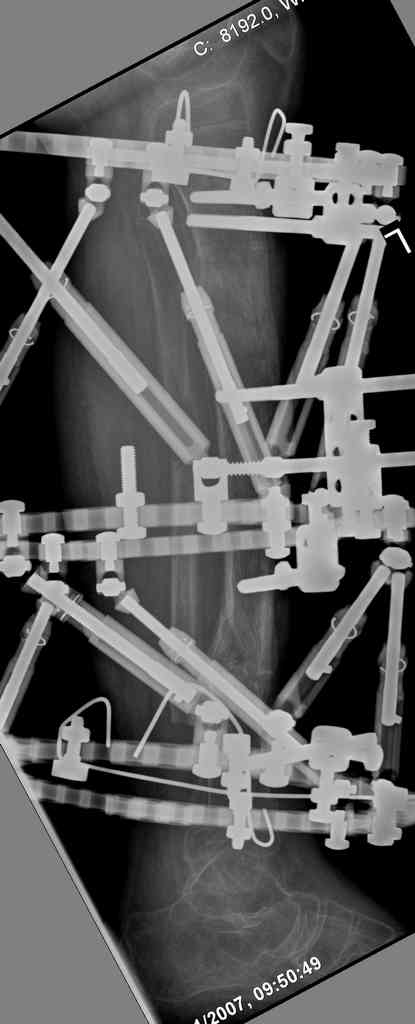

5. Ну и чтобы не быть голословным. Молодой человек подорвался на фугасе (Чечня, 2005 год). Свежие рентгенограммы:

Соответственно ожоги и дефект мягких тканей, переломы костей стопы и пр. Наложили аппарат

Илизарова (как придется), хирургически обработали и героически заживляли мягкие ткани с многочисленными кожными пластиками. В итоге через полгода я принял его вот таким:

Реализовал описанную выше методику, и в итоге вот что получилось. Высылаю лишь прямые проекции,

Очень пригодились карбоновые кольца (Джолдас -огромное спасибо, я твой должник!!!), поскольку остеопороз дистального отломка был просто невероятный. На цифровом рентгене с трудом угадывались контуры.

Рентген в процессе перемещения - внизу карбоновые кольца, тракция фрагмента спицами с упором.

внешний вид в аппарате - не завершающем этапе, сначала стопа тоже была фиксирована в аппарате.